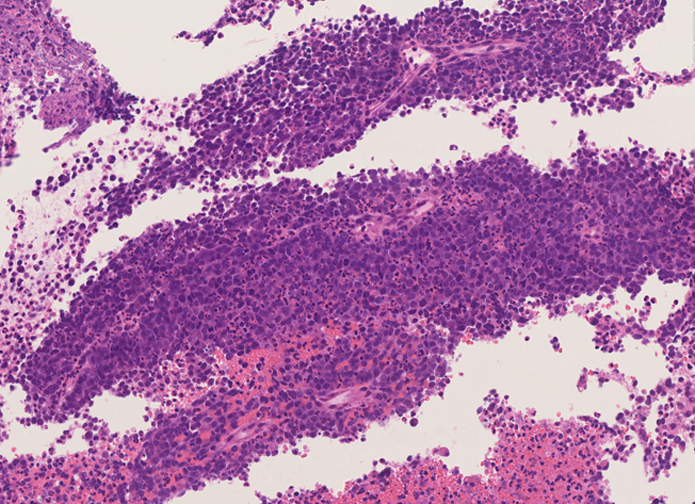

副鼻腔腫瘤生検組織

日本病理学会中部支部交見会のスライドより。(S.Suzuki Dr.)

NUT03.jpg NUT04.jpg